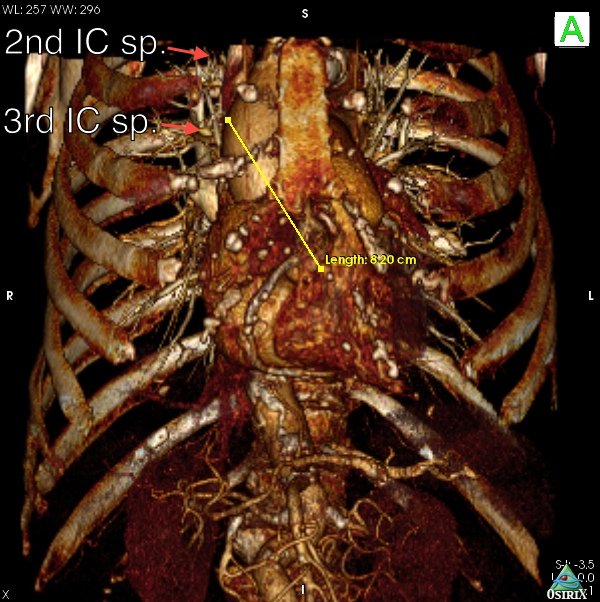

Fig. 6B: Case 2. The 3D volume rendering images revealed the right-sided and horizontal anatomy of the ascending aorta; this suggested that the optimal incision was a right upper mini-thoracotomy approach through the 2nd intercostal space.